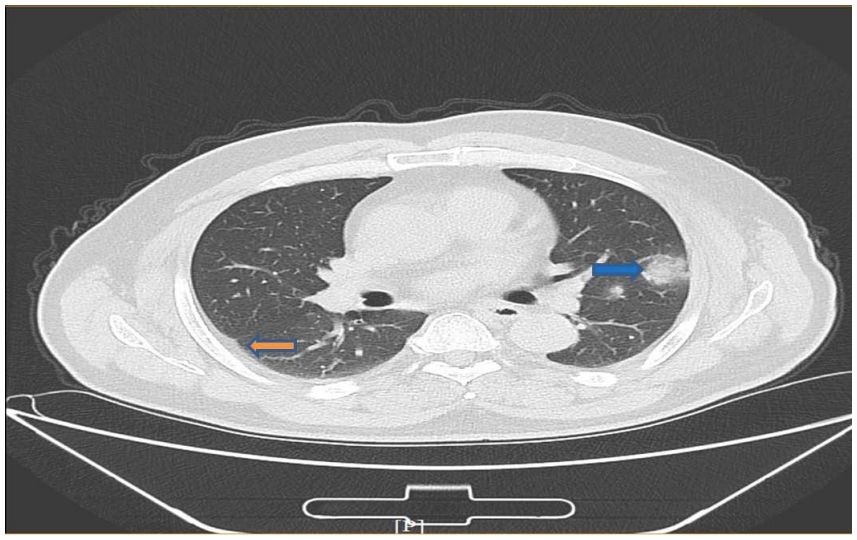

新冠肺部ct

新冠肺部ct,

电子书精选新冠肺炎ct早期征象与鉴别诊断

新型冠状病毒型肺炎患者的ct表现

两女子没得新冠但肺部ct呈毛玻璃影,医生一查原因无语了